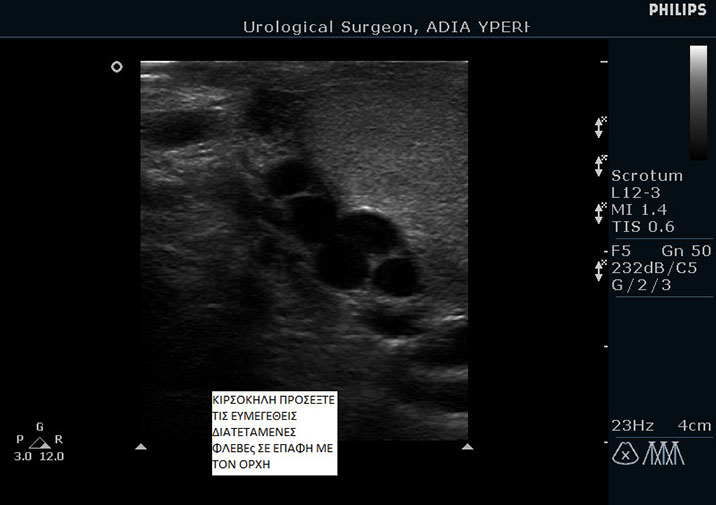

Η διάγνωση της κιρσοκήλης γίνεται πάντα από ουρολόγο με την βοήθεια έγχρωμου υπερηχογραφήματος TRIPLEX.

Ασθενής με κιρσοκήλη 3ου βαθμού.

Παρατηρήστε πως διαγράφονται οι φλέβες εντός του οσχέου. Παρακάτω μπορείτε να δείτε το triplex του ίδιου ασθενή.